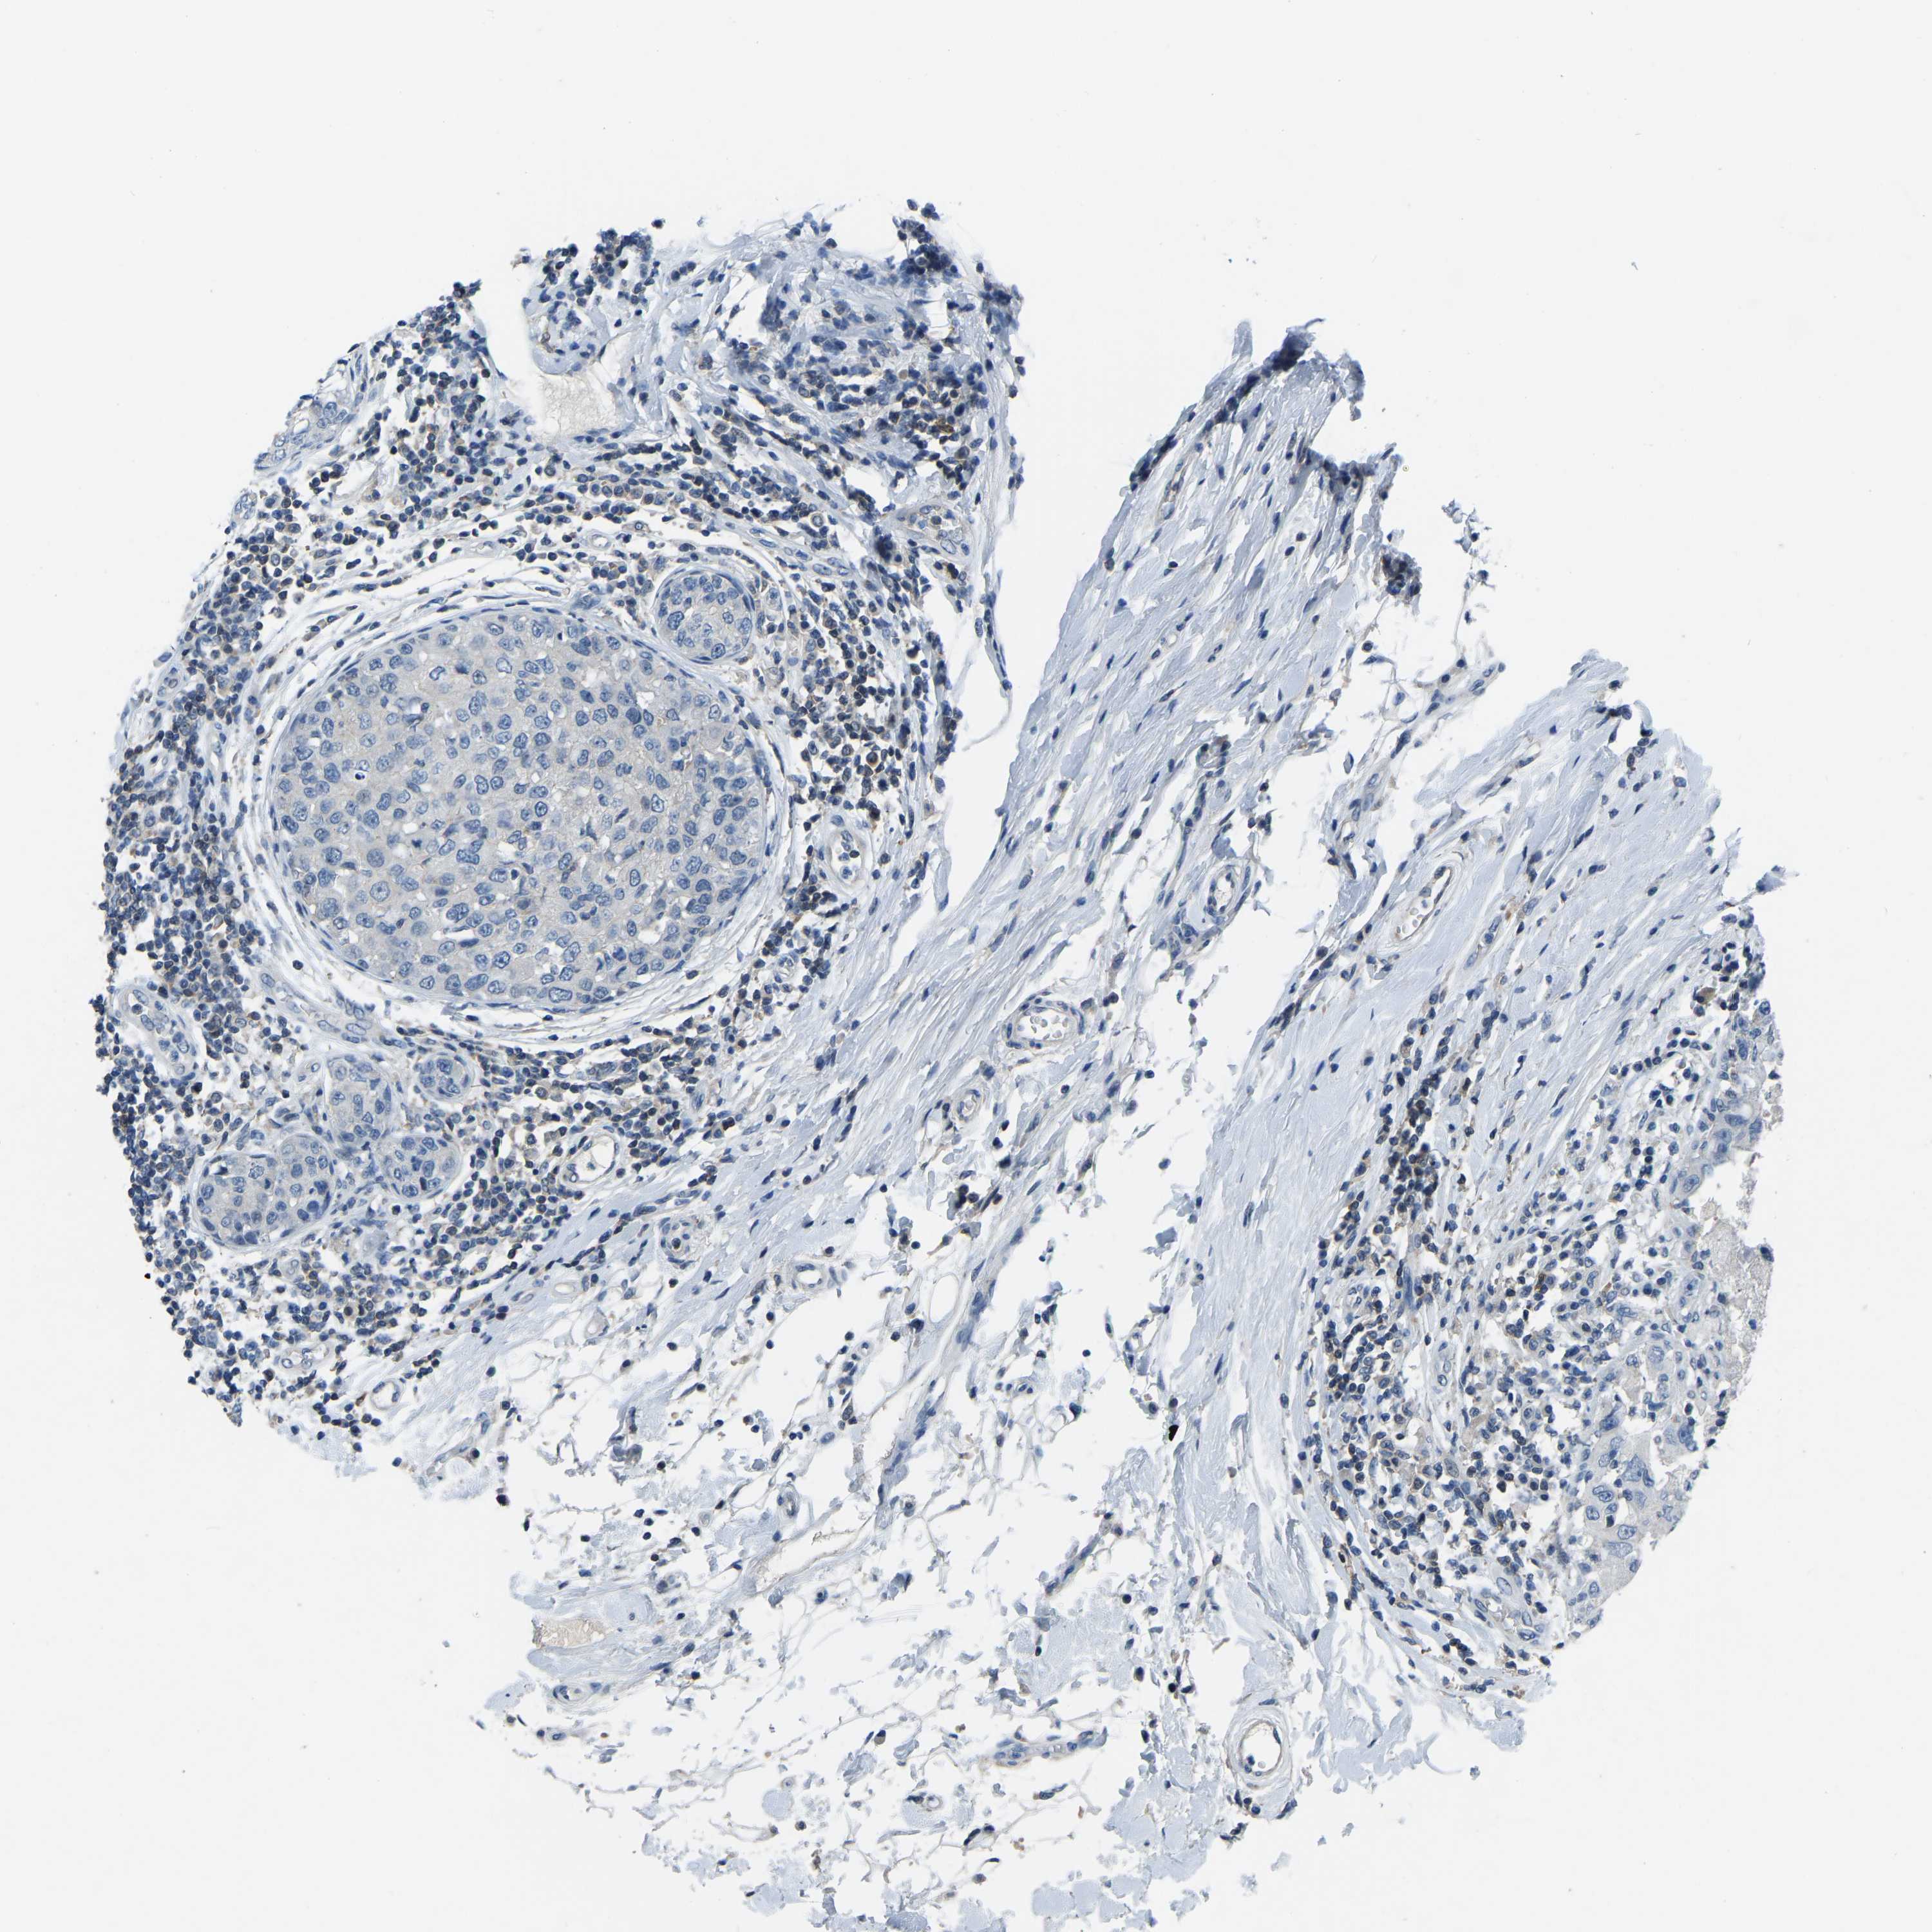

CANCER BREAST CANCER Show tissue menu

BRCA TCGA BRCA VALIDATION PROTEIN EXPRESSION

ANTIBODIES

AND

VALIDATION